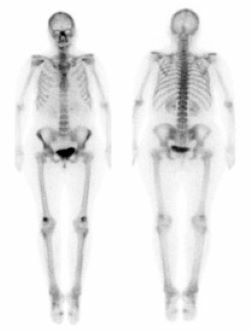

Nuclear medicine bone scan

Nuclear medicine is a subspecialty within radiology. It comprises diagnostic examinations that result in images of body anatomy and function. The images are developed based on the detection of energy emitted from a radioactive substance given to the patient, either intravenously or by mouth. Generally, radiation to the patient is similar to that resulting from standard X-ray examinations.

What are the use for Nuclear Medicine?

The list below includes many of the nuclear medicine examinations available.

• Myocardial Perfusion Scan (a.k.a. Exercise/Pharmacologic Stress Scan)

• Bone Scan

• Hepatobiliary Scan

• Lung Scan

• Renal Scan for High Blood Pressure or Captopril Renogram

• Thyroid Scan and Iodine Uptake

• White Blood Cell Scan

• Galium Scan

• GI Bleeding Scan

• Gastric Emptying Study

• Parathyroid Scan

• Oncoscint

• Octreoscan

• Nuclearcisternogram